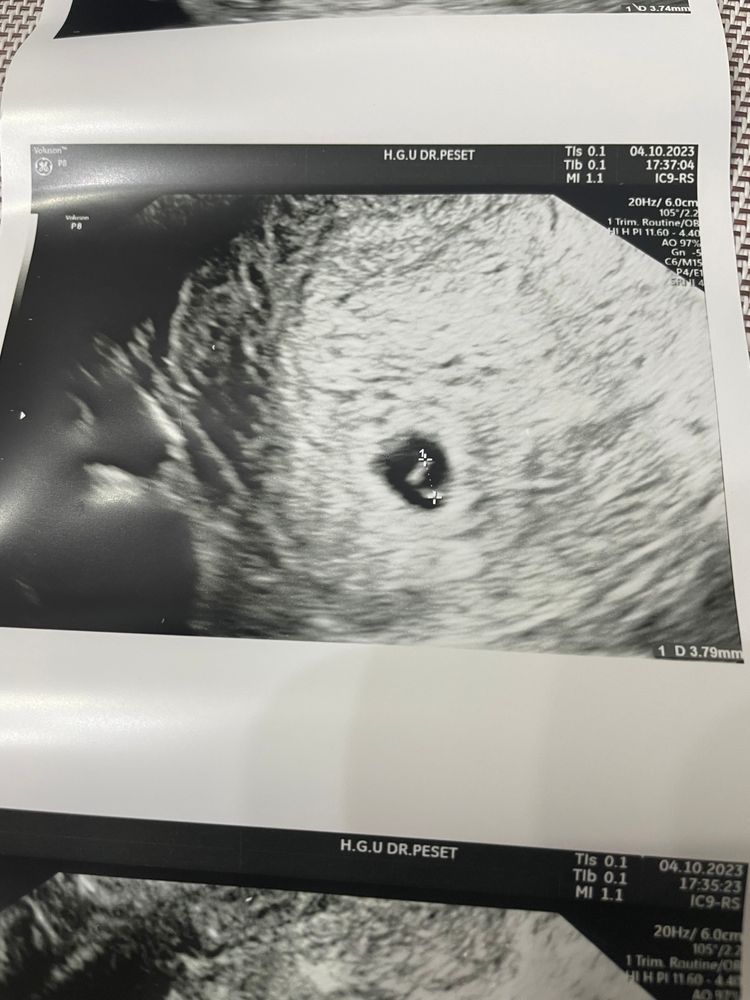

Девочки,срок 6 недель. Утром писала за резкую отмену дюфастона(по незнанию). В понедельник отменила,а сегодня утром увидела мазню. Моя врач онлайн сказала пить ВИДАНОЛ. Но в Испании мне не продали без рецепта. В ургенции мне сказали не пить никаких таблеток и это старая кровь,которая никак не вредит. В понедельник было только ПЯ,без эмбриона. А сегодня увидели 2 эмбриончика -3 мм(под вопросом). Получается,что я не навредила малышам? Если в понедельник их не было?